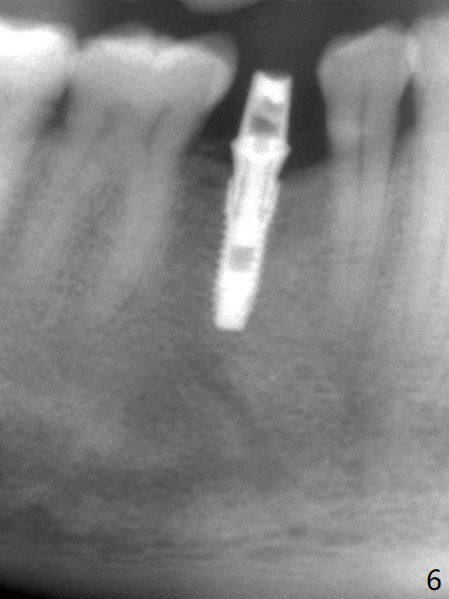

The base of the edentulous ridge at #29 looks wide (Fig.1), but the most coronal portion is the thin soft tissue (Fig.2).  It appears that there has been bone resorption since extraction.  The initial osteotomy depth is 11.5 mm (Fig.3).  Since the Mental Loop seems to be nearby, the depth of subsequent osteotomy (3 mm) remains the same (Fig.4).  Although the final depth of osteotomy is 13 mm, the implant placed is short (3.8x11.5 mm, Fig.5,6), as compared to the immediate implant (3.8x18 mm) at the contralateral side (#20).  There is mild bone resorption mesially 4 months postop (Fig.7).  The crown is loose (poor osteotomy position, guide necessity) 7 months post cementation immediately prior to 18 cementation, although there is no gross bone losss 1 year 7 months post cementation (Fig.8).